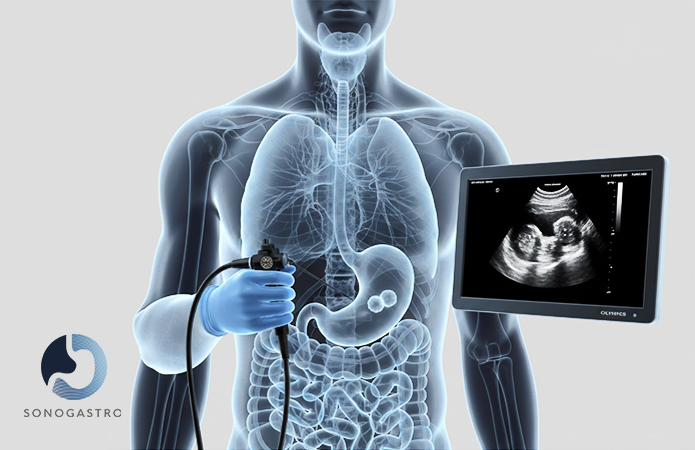

Endoscopic ultrasound (EUS) for pancreatic, biliary, and gastrointestinal conditions.

Diagnostic and therapeutic upper endoscopy.

Guided endoscopic tissue sampling when clinically justified.